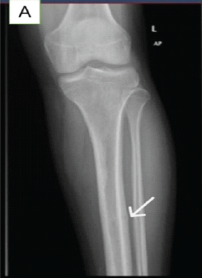

Diagnostic Pitfalls: Anterior Tibial Stress Fracture in a Professional Football Player – A Case Report

Zakir Ali Shah , Badr Al Hammadi , Habib Al Ismaily , Abdulla Nidal , Khaled Al Madani , Zainab Al Jawi